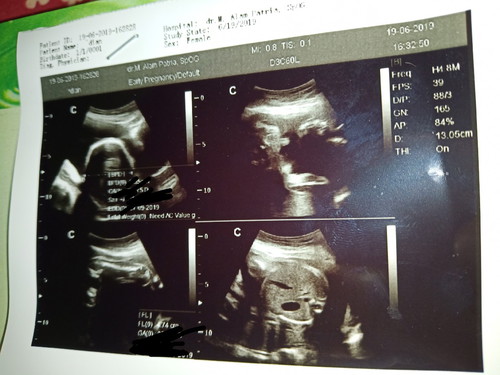

hasil usg

Ini hasil usg ku bund,, katanya anakku laki2, soalnya keliatan bngt tonjolan itu nya,, suami pengen nya laki2,,, 25 week